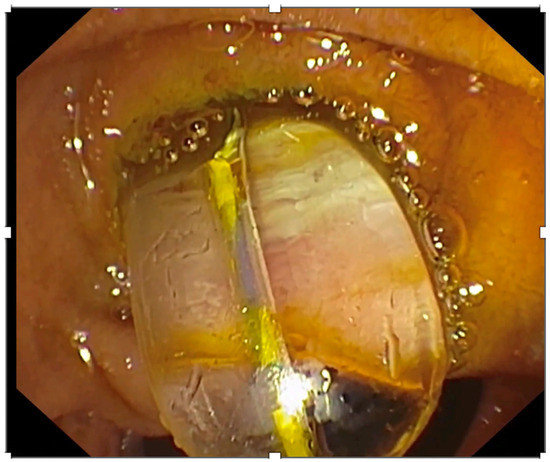

- Kamiyama, R.; Ogura, T.; Okuda, A.; Miyano, A.; Nishioka, N.; Imanishi, M.; Takagi, W.; Higuchi, K. Electrohydraulic Lithotripsy for Difficult Bile Duct Stones under Endoscopic Retrograde Cholangiopancreatography and Peroral Transluminal Cholangioscopy Guidance. Gut Liver 2018, 12, 457–462. [Google Scholar] [CrossRef]

- Buxbaum, J.; Sahakian, A.; Ko, C.; Jayaram, P.; Lane, C.; Yu, C.Y.; Kankotia, R.; Laine, L. Randomized trial of cholangioscopy-guided laser lithotripsy versus conventional therapy for large bile duct stones (with videos). Gastrointest. Endosc. 2018, 87, 1050–1060. [Google Scholar] [CrossRef]

- Angsuwatcharakon, P.; Kulpatcharapong, S.; Ridtitid, W.; Boonmee, C.; Piyachaturawat, P.; Kongkam, P.; Pareesri, W.; Rerknimitr, R. Digital cholangioscopy-guided laser versus mechanical lithotripsy for large bile duct stone removal after failed papillary large-balloon dilation: A randomized study. Endoscopy 2019, 51, 1066–1073. [Google Scholar] [CrossRef]